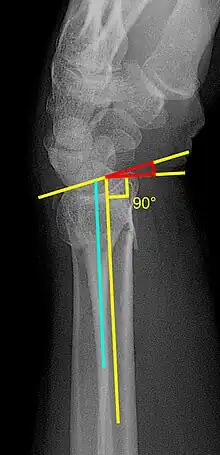

Various kinds of information can be obtained from X-rays of the wrist:[5]

Lateral view

- Carpal malalignment - A line is drawn along the long axis of the capitate bone and another line is drawn along the long axis of the radius. If the carpal bones are aligned, both lines will intersect within the carpal bones. If the carpal bones are not aligned, both lines will intersect outside the carpal bones. Carpal malignment is frequently associated with dorsal or volar tilt of the radius and will have poor grip strength and poor forearm rotation.[5]

- Tear drop angle - It is the angle between the line that pass through the central axis of the volar rim of the lunate facet of the radius and the line that pass through the long axis of the radius. Tear drop angle less than 45 degrees indicates displacement of lunate facet.[5]

- Antero-posterior distance (AP distance) - Seen on lateral X-ray, it is the distance between the dorsal and volar rim of the lunate facet of the radius. The usual distance is 19 mm.[5] Increased AP distance indicates the lunate facet fracture.[8]

- Volar or dorsal tilt - A line is drawn joining the most distal ends of the volar and dorsal side of the radius. Another line perpendicular to the longitudinal axis of the radius is drawn. The angle between the two lines is the angle of volar or dorsal tilt of the wrist. Measurement of volar or dorsal tilt should be made in true lateral view of the wrist because pronation of the forearm reduces the volar tilt and supination increases it. When dorsal tilt is more than 11 degrees, it is associated with loss of grip strength and loss of wrist flexion.[5]

Posteroanterior view

- Radial inclination - It is the angle between a line drawn from the radial styloid to the medial end of the articular surface of the radius and a line drawn perpendicular to the long axis of the radius. Loss of radial inclination is associated with loss of grip strength.[5]

- Radial length - It is the vertical distance in millimetres between a line tangential to the articular surface of the ulna and a tangential line drawn at the most distal point of radius (radial styloid). Shortening of radial length more than 4mm is associated with wrist pain.[5]

- Ulnar variance - It is the vertical distance between a horizontal line parallel to the articular surface of the radius and another horizontal line drawn parallel to the articular surface of the ulnar head. Positive ulnar variance (ulna appears longer than radius) disturbs the integrity of triangular fibrocartilage complex and is associated with loss of grip strength and wrist pain.[5]

Oblique view

- Pronated oblique view of the distal radius helps to show the degree of comminution of the distal end radius, depression of the radial styloid, and confirming the position the screws at the radial side of the distal end radius. Meanwhile, a supinated oblique view of shows the ulnar side of the distal radius, accessing the depression of dorsal rim of the lunate facet, and the position of the screws on the ulnar side of the distal end radius.[5]